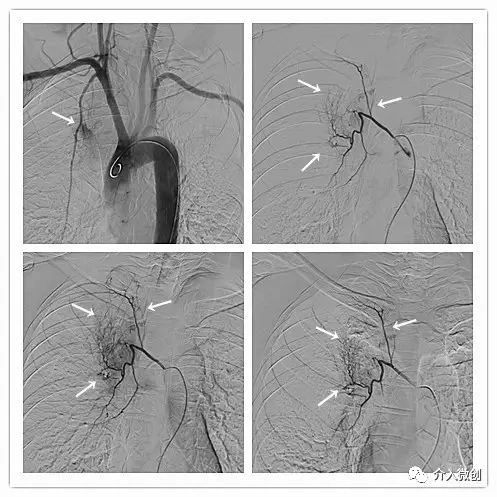

DSA下行支气管动脉化疗灌注治疗

术前CT显示纵膈肿物,包绕、压迫纵膈血管